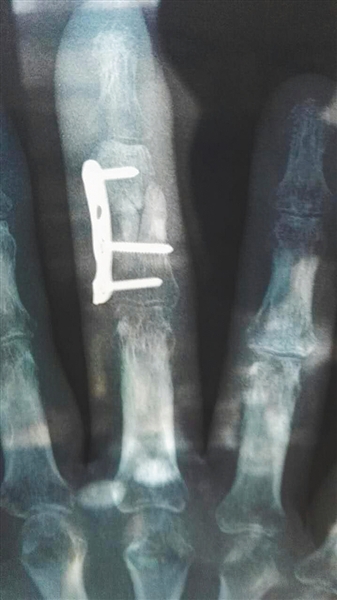

杨先生3月5日所照的X光片显示伤处仍未愈合。

杨先生去年12月手指骨折在北京积水潭医院就医,但随后仅凭借一张医生手写字条就被介绍到北京国济中医医院做手术。